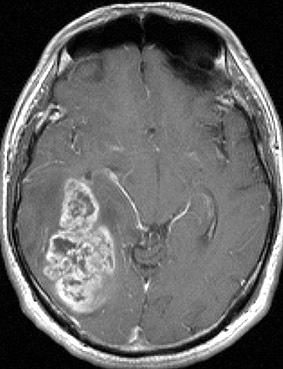

典型的な膠芽腫のガドリニウム増強画像です。右の側頭葉から発生したために目立った症状が無く,この大きさで発症しました。何となくボッとしていると言うのが訴えでした。腫瘍の周囲がガドリニウムで白く増強されて,内部は壊死で低信号(黒っぽい)になっています。

• ガドリニウム造影剤で腫瘍の周辺が白く造影されます

• いびつな形になるのが特徴です

• しかし,ほんとうの腫瘍の広がりは,T2強調あるいはFLAIR(フレア)という画像で,白く滲むように写る部分すべてです